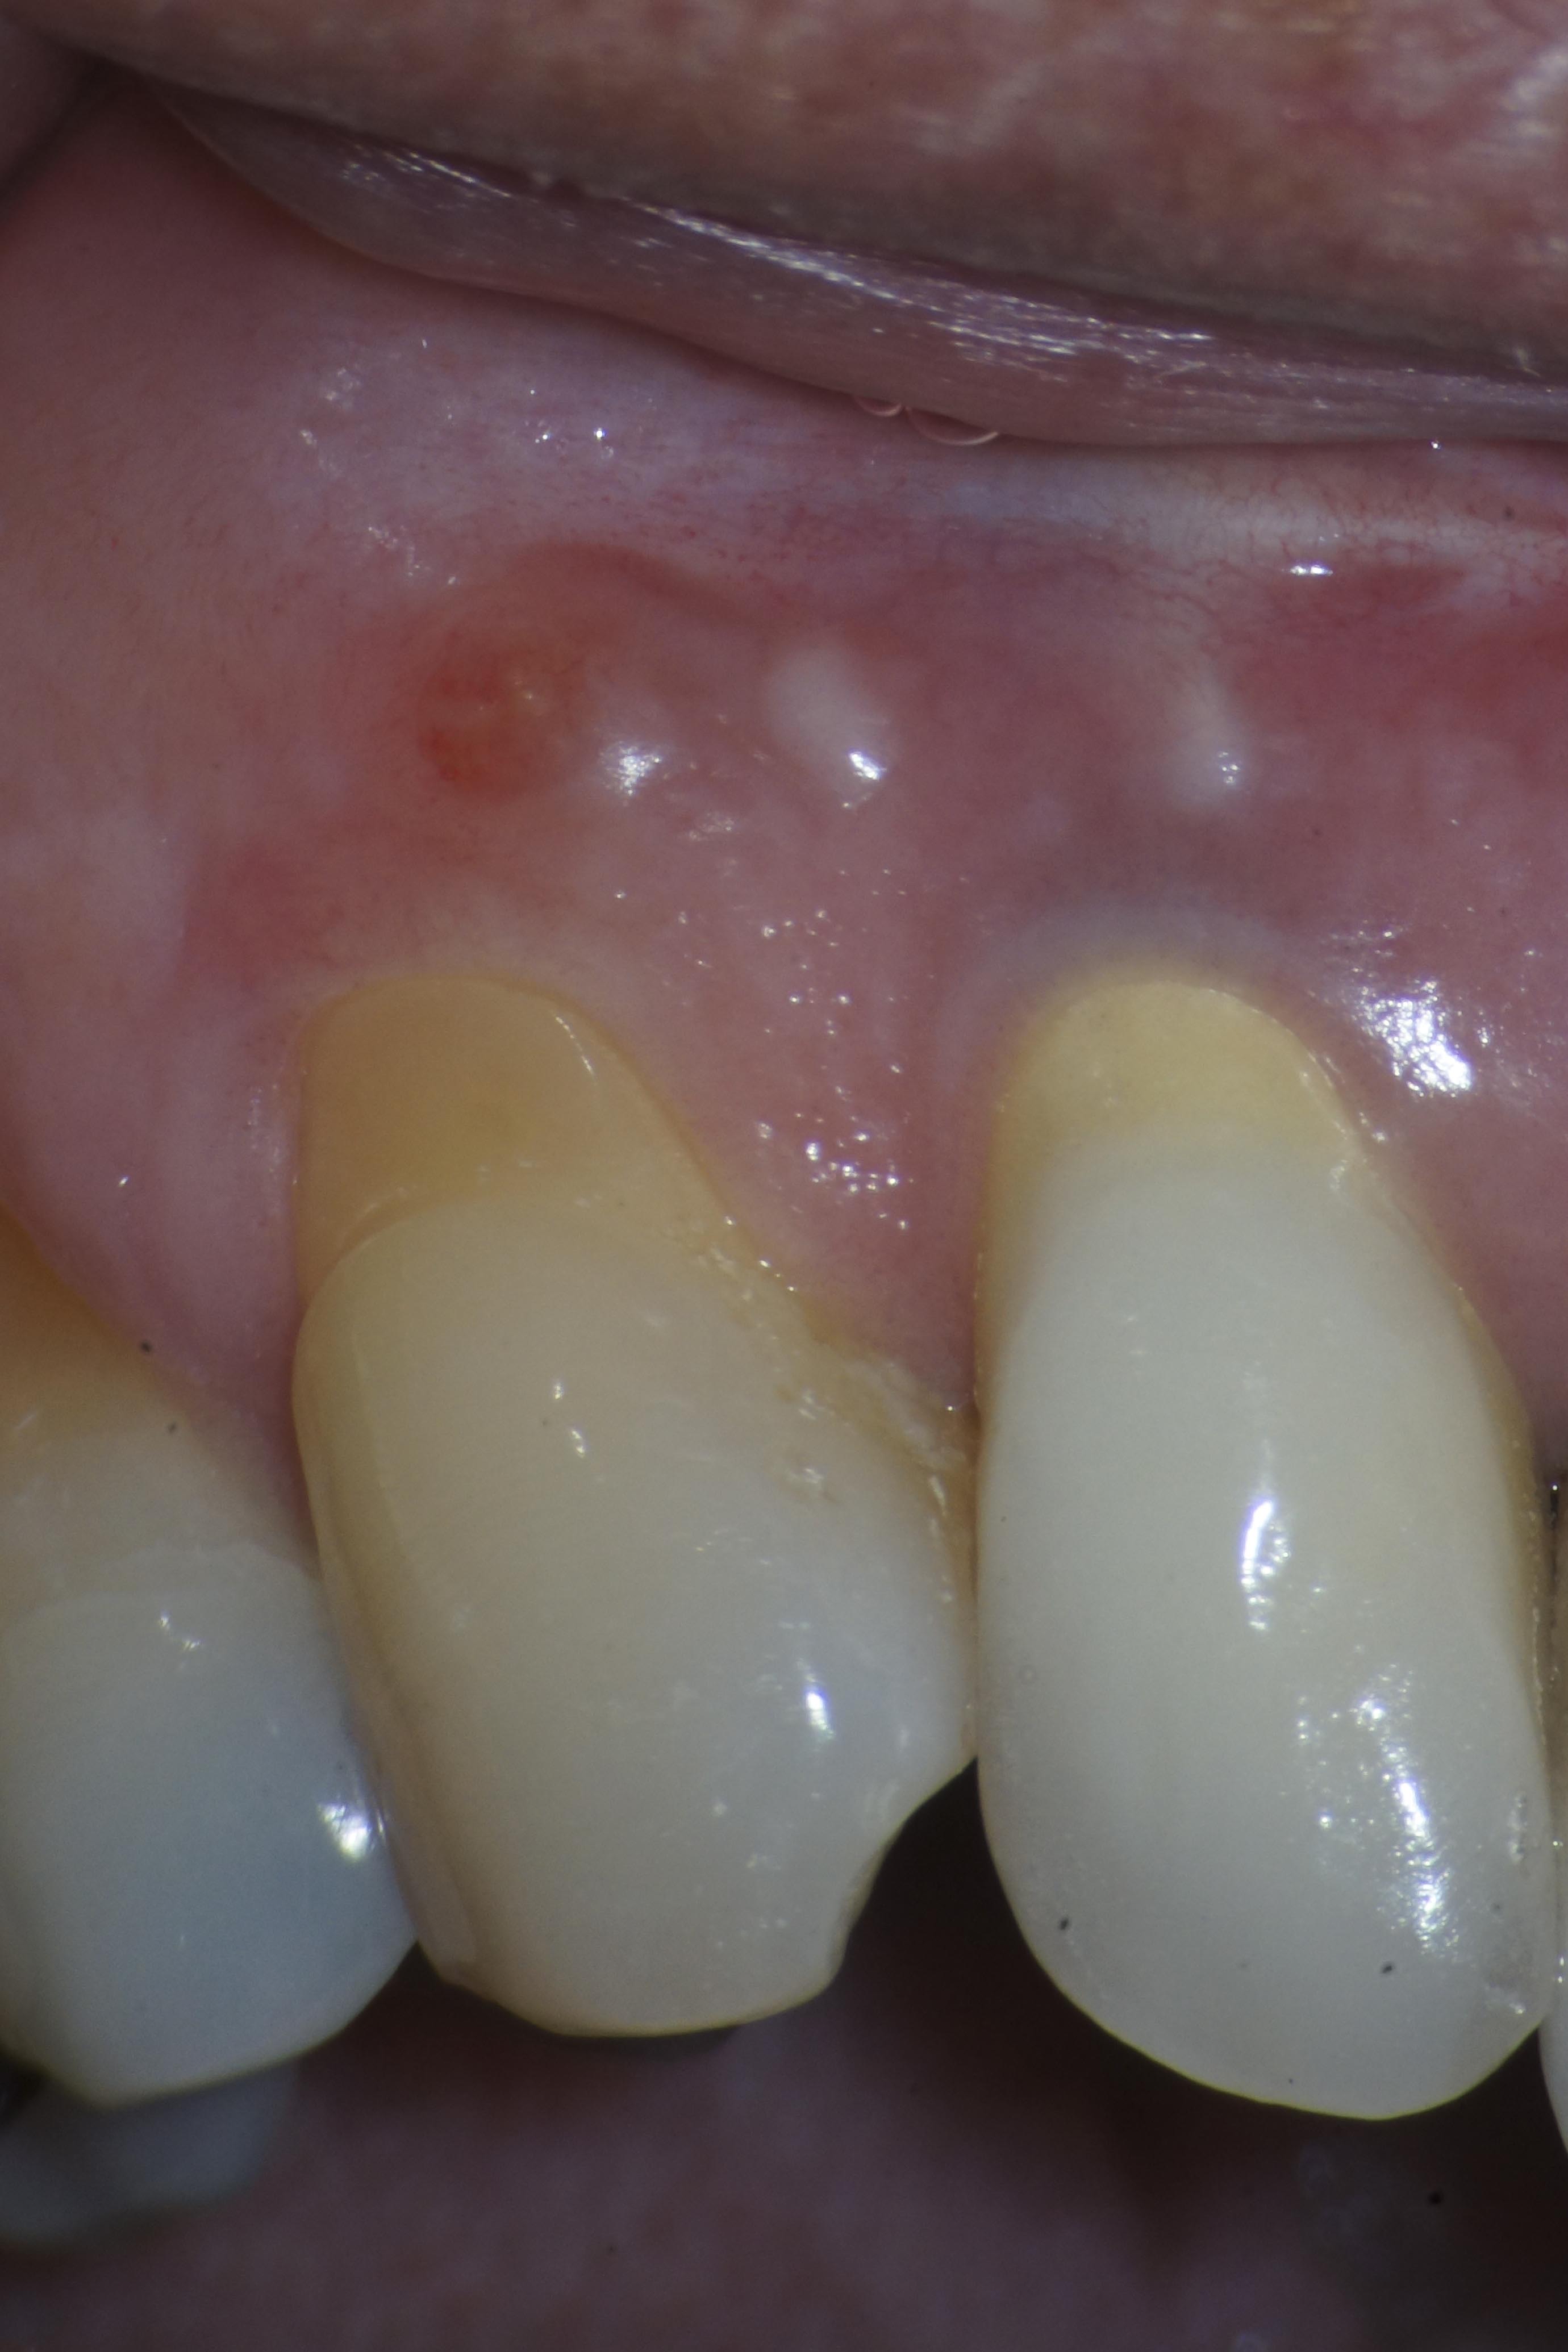

KU13-1 Veröffentlicht 12. Februar 2014 am 2760 × 4140 in Neue Wege gehen Symptomatischer Zahn 13 mit Fistel